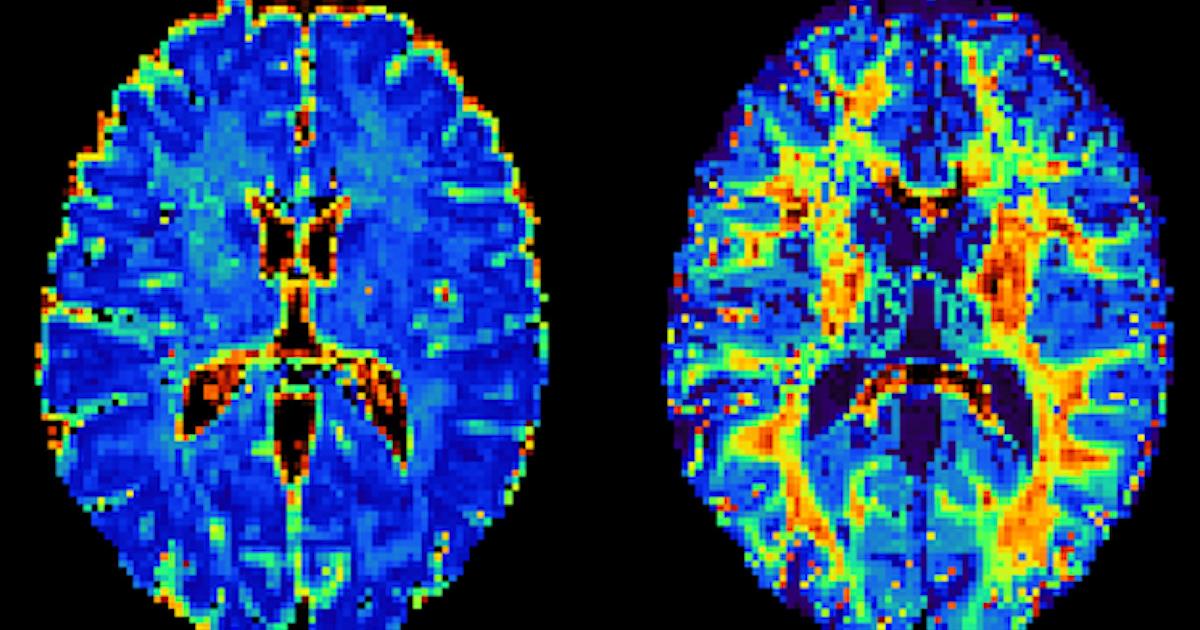

Cortical microstructure quantified in vivo in the human brain using #NEXI on a #Connectom scanner 🧠🧲🔍 Congrats Quentin Uhl for the 1st paper of your PhD! #MicMapLab A fruitful collaboration w/ MarcoPalombo @Dee_Kay_Jay Malwina Molendowska Swiss National Science Foundation #Eccellenza CHUV / Centre hospitalier universitaire vaudois